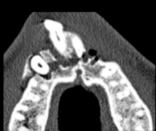

CBCT

Cone Beam Computed Tomography used for detailed imaging of dental structures.

imaging for fractures

PA to CBCT

alveolar fracture

difficult to visualize on 2D

bone with tooth fractured